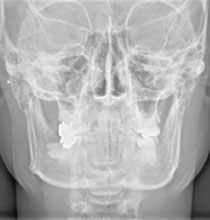

広範囲の撮影が可能なCT(3D撮影)機器です。3D撮影によって多角的な診断が実現し、親知らずの抜歯やインプラント治療、根管治療などの複雑な治療を安全・正確に行うことができます。デジタル方式を採用しているため低被ばくで、被ばく量は従来の機器と比べて大幅に減少しています。

セファロ(正面)